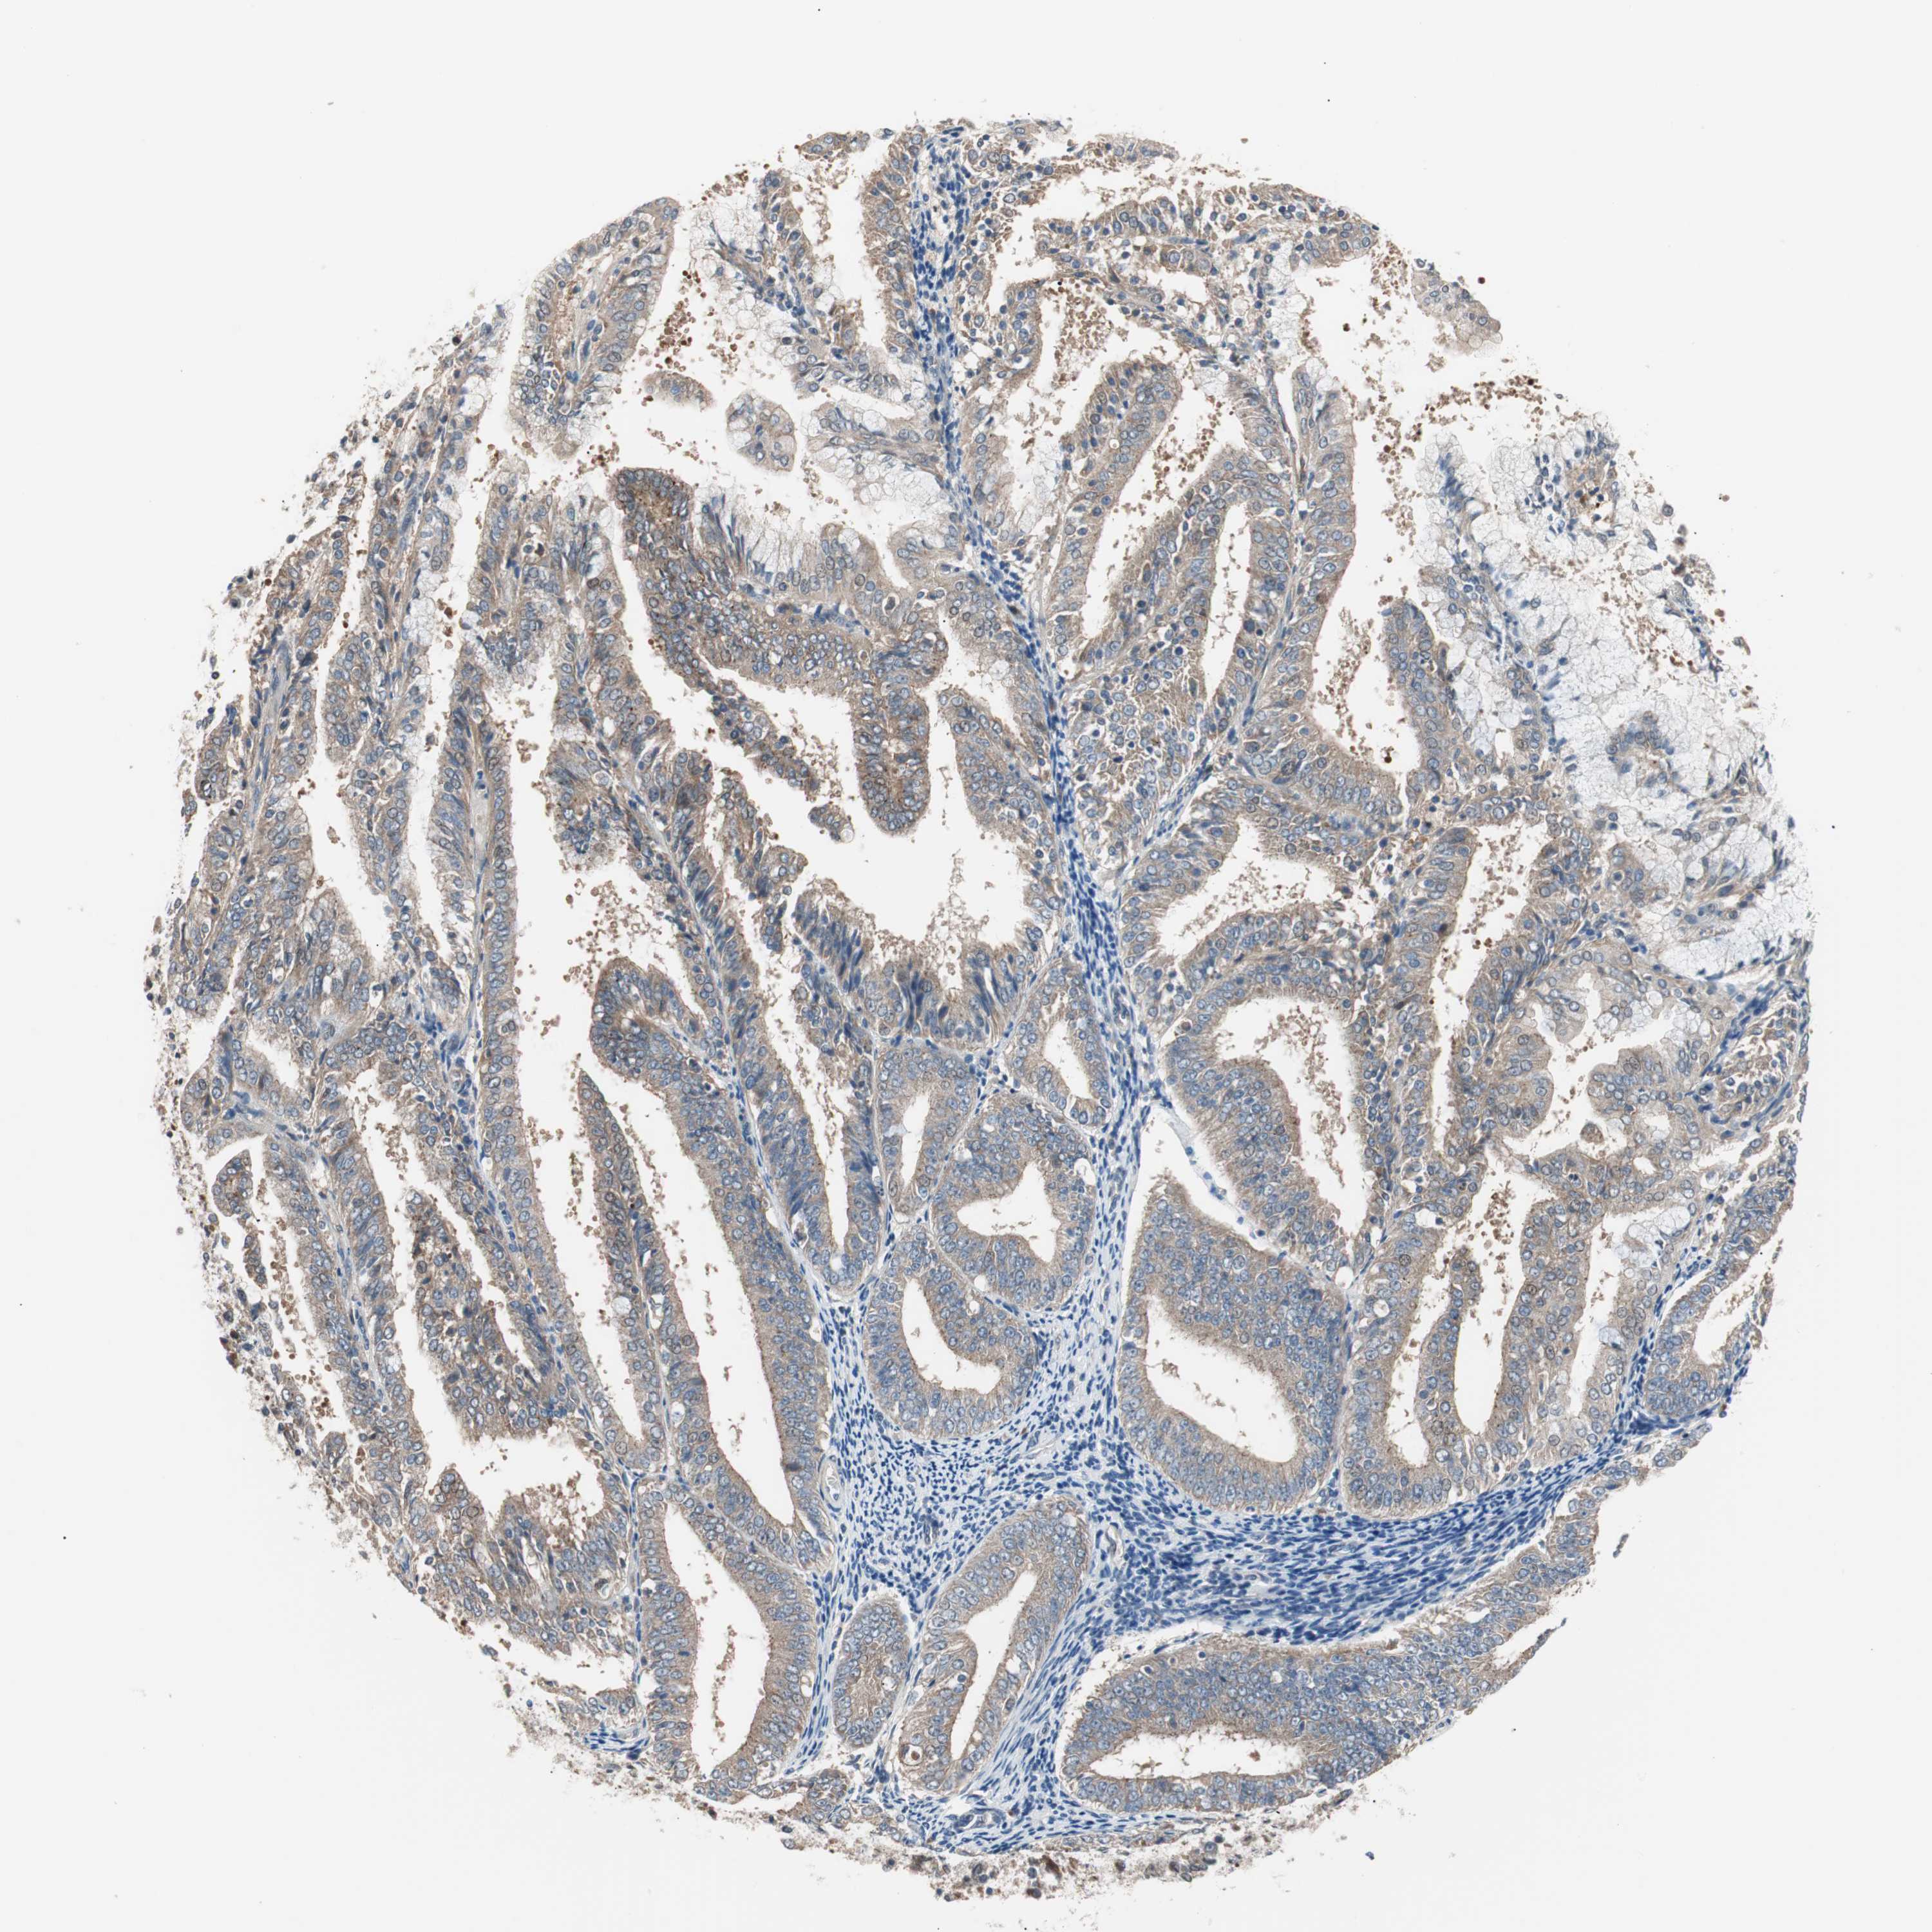

ENDOMETRIAL CANCER - Protein expressioni

A mouse-over function shows sample information and annotation data. Click on an image to view it in a full screen mode. Samples can be filtered based on level of antibody staining by selecting one or several of the following categories: high, medium, low and not detected. The assay and annotation is described here.

Note that samples used for immunohistochemistry by the Human Protein Atlas do not correspond to samples in the TCGA dataset.

Antibody stainingi

Antibody staining in the annotated cell types in the current human tissue is reported as not detected, low, medium, or high, based on conventional immunohistochemistry profiling in selected tissues. This score is based on the combination of the staining intensity and fraction of stained cells.

Each image is clickable and will lead to virtual microscopy that enables deeper exploration of all samples and also displays staining intensity scores, fraction scores and subcellular localization as well as patient and tissue information for each sample.

Antibody HPA006277

Antibody HPA006507

Antibody CAB017027

Staining

High

Medium

Low

Not detected

Intensity

Strong

Moderate

Weak

Negative

Quantity

>75%

75%-25%

<25%

None

Location

Nuclear

Cytoplasmic/membranous

Cytoplasmic/membranous,nuclear

Adenocarcinoma, NOS